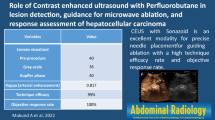

Abstract

Objectives

To describe the early patterns of liver lesions successfully treated with radiofrequency ablation (RFA) or cryoablation (CA) and their changes over time.

Methods

Twenty-two RFA-treated and 17 CA-treated patients underwent CEUS from week 1 to year 3 post-ablation. Patterns, margins and volumes of RF-induced and cryolesions were evaluated and compared over time.

Results

After contrast enhancement, shortly after ablation, undefined margins with persistent enhancing small vessels penetrating >2 mm into the treated zone were significantly more frequent after CA (67 %) than RFA (22 %) (P < 0.02). During the arterial phase, a thin, enhancing marginal rim was seen during week 1 (T1) in around 28 % of RF lesions, while 75 % of cryolesions had thick enhancing rims (P < 0.02). The mean RF-induced lesion volume, maximum at T1 (44.1 ± 37.5 ml), shrank slowly over time, remaining clearly visible at 1 year (8.3 ± 7.4 ml). Cryolesions shrank faster (P = 0.009), from an average of 16.6 ± 7.1 ml at T1 to 1.7 ± 1.3 ml 1-year post-ablation.

Conclusion

RF-induced and cryolesions differ, particularly their margins and shrinkage rates. Knowing these differences allows avoidance of incomplete treatment or falsely diagnosed recurrence, especially after CA.